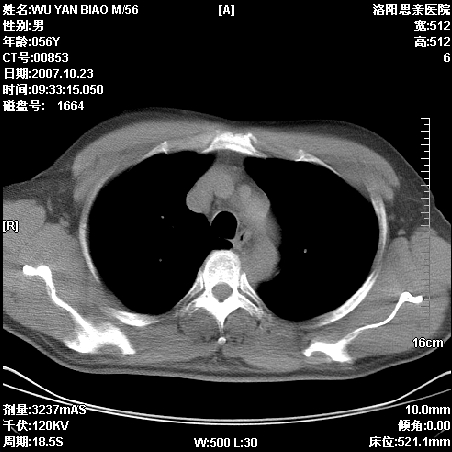

标题: CT10160:M56Y,体检发现,病人无不适,病人随访中 [打印本页]

标题: CT10160:M56Y,体检发现,病人无不适,病人随访中

后上纵隔占位,与肺交界清,宽基底附着脊柱,密度均匀,局部骨质无明确改变.

考虑;神经源性肿瘤,---起源交感n链?,不除外肠源性囊肿.

1、病灶在后纵隔脊柱旁沟内,此处是神经原性肿瘤的好发部位

2、病灶边缘光滑整齐,更说明病灶来于纵隔,由于有胸膜的包裹所以才导致这么光滑的边缘

3、病灶内的密度均匀